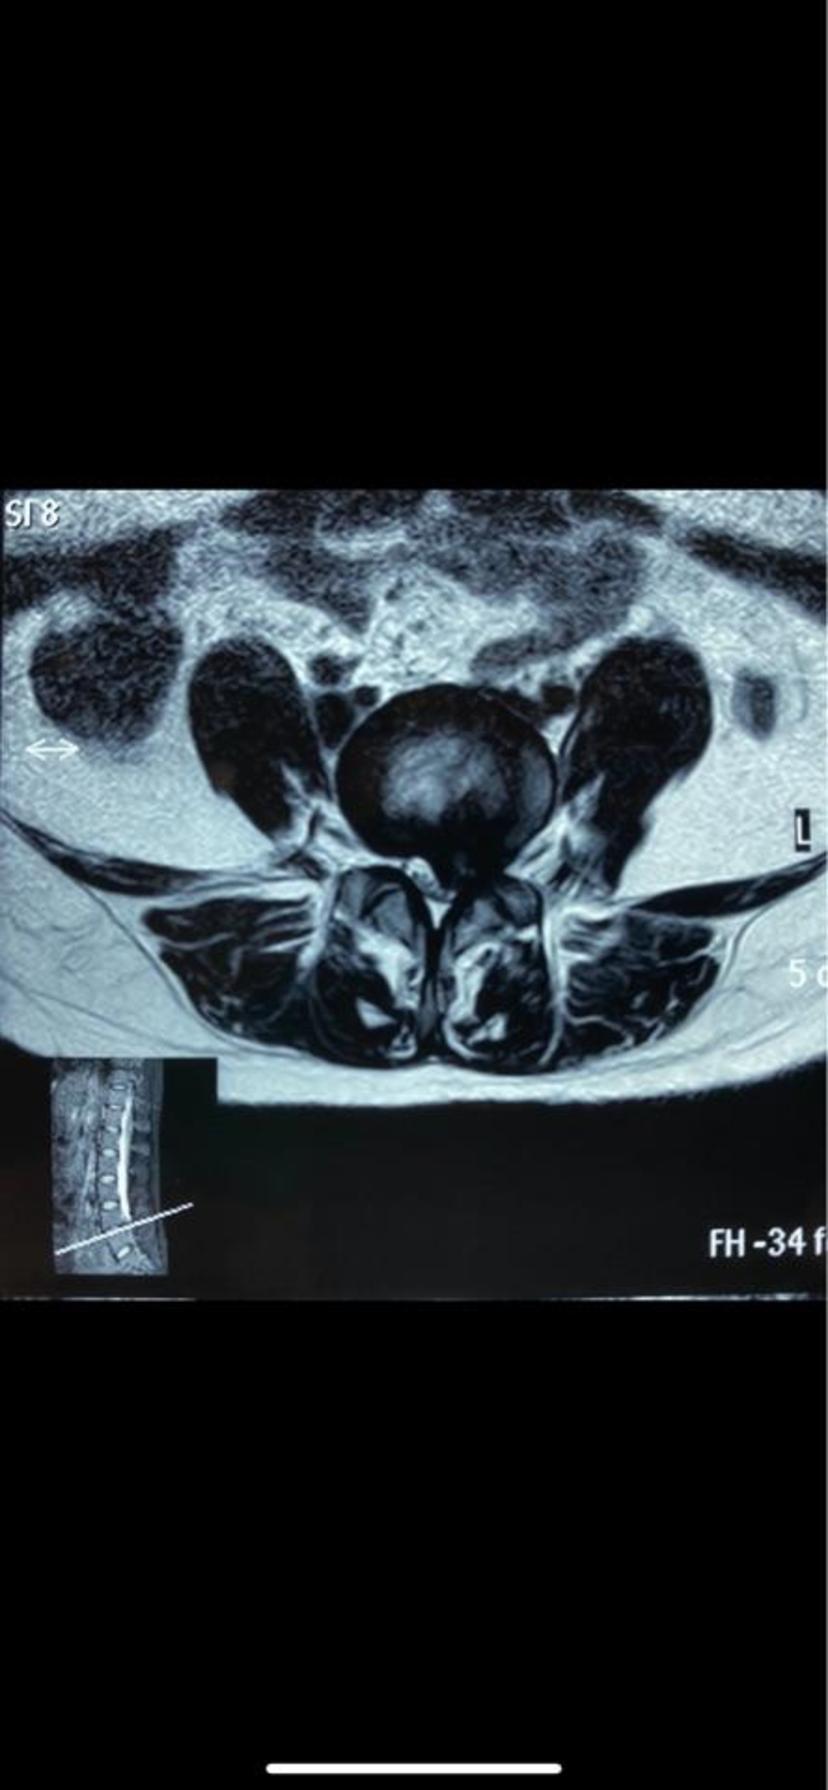

磁共振显示突出物占满整个椎管,继发椎管狭窄